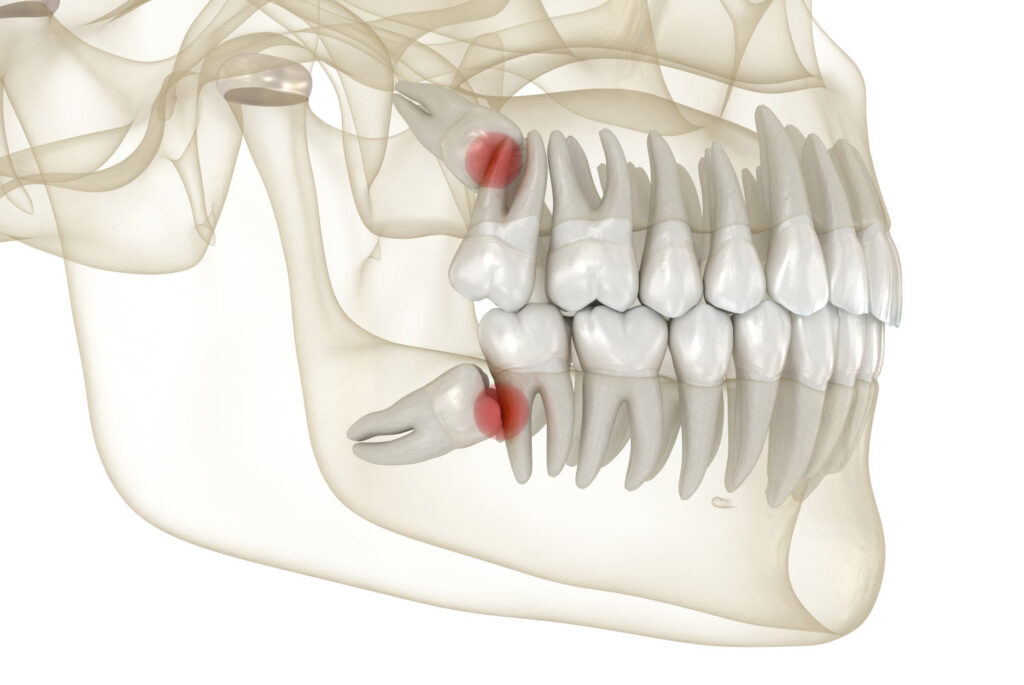

extracția molarilor de minte incluși sau semiincluși;

rezecția apicală (îndepărtarea infecțiilor de la vârful rădăcinii dentare);

molarii de minte creează presiuni, inflamații sau migrarea celorlalți dinți.